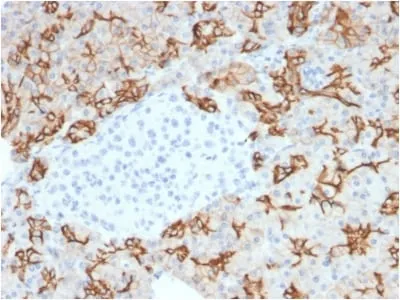

Anti-TACSTD2 / TROP2 (Epithelial Marker) (TACSTD2/2153), Biotin conjugate